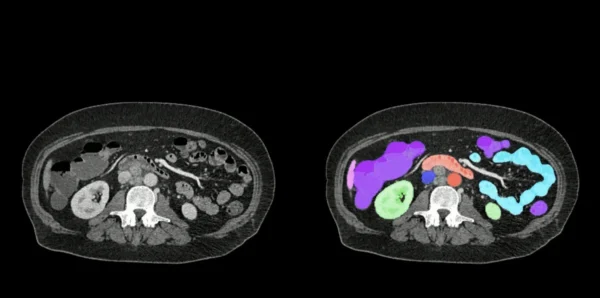

שתי סדרות של חתכי סריקות CT של הבטן – הסטנדרטית משמאל וסגמנטציית האיברים של AbdomenAtlas מימין.

כאן נכנסת לתמונה AbdomenAtlas, פרויקט חדשני שפותח על ידי צוות חוקרים מאוניברסיטת ג'ונס הופקינס, בראשות הפרופסור אלן יואל. מדובר במאגר הדמיות CT הגדול ביותר שנוצר אי פעם, הכולל מעל 45,000 סריקות של 142 מבנים אנטומיים שונים שנאספו מ-145 בתי חולים ברחבי העולם. בהשוואה למאגר הנתונים הקודם בתחום (TotalSegmentator V2), AbdomenAtlas גדול יותר פי 36 ומאפשר דיוק חסר תקדים בזיהוי מבנים בבטן.